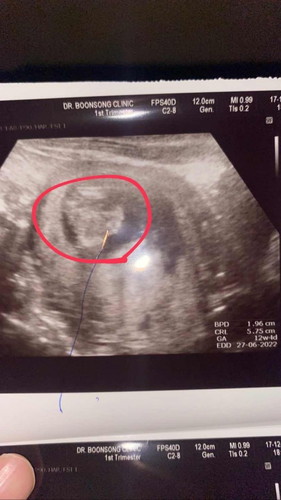

ผนังหน้าท้องไม่ปิด

แม่ๆบ้านไหน ที่ผนังหน้าท้องลูกไม่ปิดบ้างค่ะ อยากรู้ประสบการ เป็นยังไงกันค่ะ ช่วยแชร์ให้ทีนะค่ะ ขอบคุนค่ะ